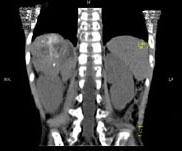

问题 男,5 岁,消瘦、贫血、纳差和腹部包块3个月,CT检查如图,下列说法正确的是 ( )

选项 A、该病灶来源于右肾上腺,考虑为神经母细胞瘤 B、该病灶来源于右肾,考虑为肾胚胎瘤 C、肿块密度不均匀,可见片状的较高密度,考虑为出血,也可见点状的钙化影 D、该病灶来源于肝脏,考虑为肝母细胞瘤 E、右侧腹腔内可见一巨大软组织肿块影,其边界欠清楚

答案 ACE